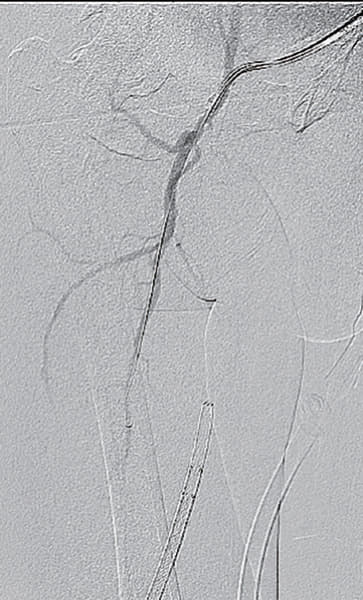

- マイクロカテーテルは硬化した閉塞部を通過せず、metal tip typeのマイクロカテーテルも通過しなかったことから、ブロッケンブロー針にて病変通過(図4)